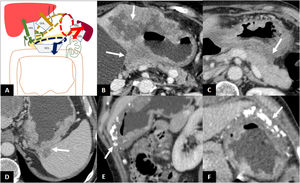

GAs located in the cardia and the lesser curvature can disseminate along the gastrohepatic ligament (GHL), those located in the antrum or pylorus along the hepatoduodenal ligament (HDL), those located in the greater curvature along the gastrocolic ligament (GCL) (and spread to the greater omentum), and those located in the fundus and the upper region of the greater curvature along the gastrosplenic ligament (GSL), and from there to the splenorenal ligament (SRL) (Fig. 5)1.

Subperitoneal dissemination. A) Illustration of the perigastric ligaments as possible routes of subperitoneal dissemination of gastric adenocarcinoma. GSL: gastrosplenic ligament; GCL: gastrocolic ligament; SRL: splenorenal ligament; GHL: gastrohepatic ligament; HDL: hepatoduodenal ligament; 1: neoplasm in cardia and lesser curvature; 2: antro-pyloric neoplasm; 3: neoplasm in greater curvature; 4: neoplasm in fundus and upper region of the greater curvature. B) Infiltration of the GHL: increased nodular density surrounding the left gastric vessels. B') Illustration of B showing soft tissue surrounding the left gastric vessels suggesting infiltration of the ligament (arrow). C) Infiltration of the HDL: soft tissue surrounding the portal vein and hepatic artery in the hepatic hilum. D) GSL infiltration: increased density surrounding the short gastric and left gastroepiploic vessels. E) SRL infiltration: soft tissue surrounding the splenic vessels.